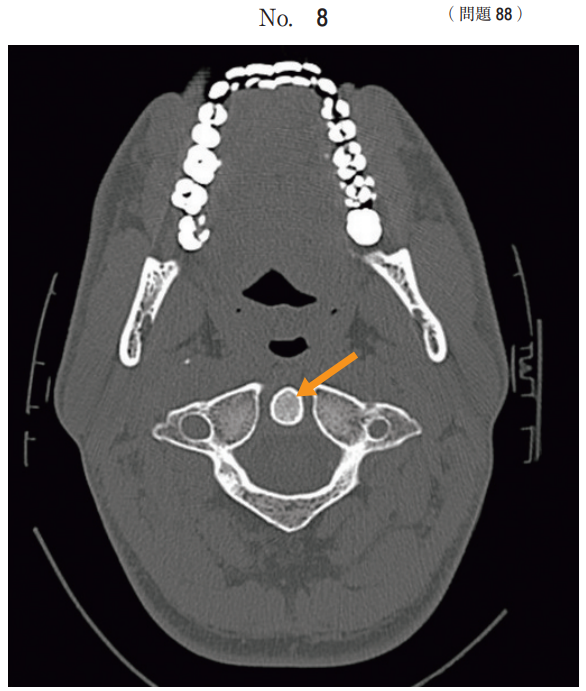

午前/問題88

頸部の単純 CT 像(別冊No. 8)を別に示す。

矢印で示すのはどれか。

1.横突起

2.棘突起

3.筋突起

4.歯突起

5.乳様突起

答え

4